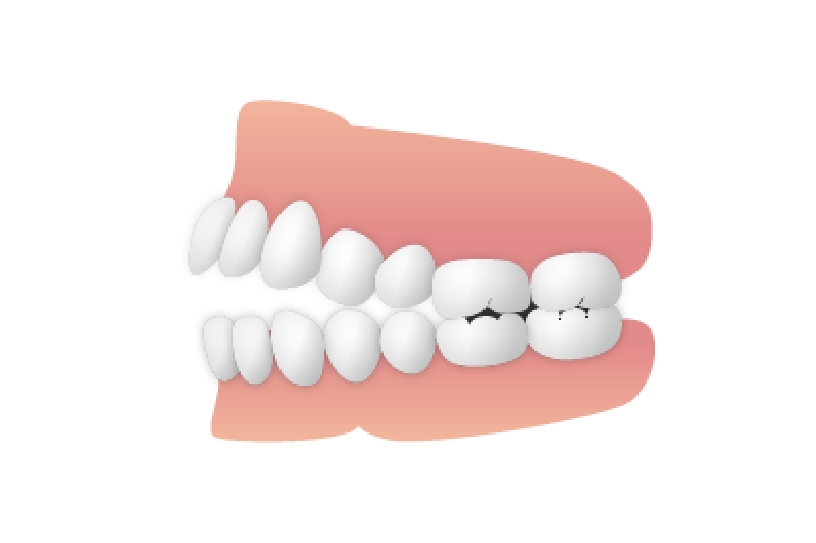

下顎前突(かがくぜんとつ)

下顎前突

下顎が突き出ているケースで、いわゆる「受け口」になります。顎の成長が終わる前に治療を始める必要があり、最悪の場合、顎の骨を切断する大がかりな手術を要します。成長期であれば、「チンキャップ」と呼ばれる帽子状の器具をはめて、突出を抑えるようにします。

下顎前突 治療後

主訴 顎が出ていて見た目が気になる

診断名あるいは主な症状 下顎前突

年齢 11歳9ヶ月

治療に用いた主な装置 ブラケット装置 スタンダードエッジワイズ法

抜歯部位 非抜歯

治療期間 3年2ヶ月

治療費概算 70万+月々の調整料

リスク副作用 歯の根が吸収して短くなる場合があります。

歯茎が痩せて下がる場合があります。

舌で歯を押す唇を噛む等の癖が改善されない場合は、治療期間が長引く場合があります。

定期的に通院できない、キャンセルが多い場合は治療期間が長引きます。